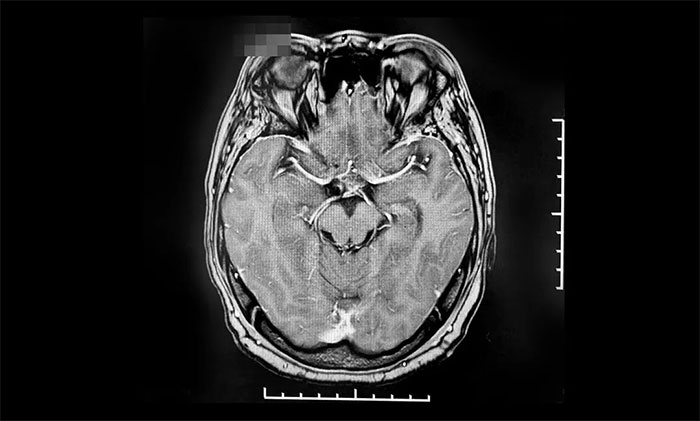

六旬男子突发言语不清,肢体活动障碍 原来是烟雾病“作祟”

烟雾病是一组以双侧颈内动脉末端和(或)大脑前动脉、大脑中动脉起始部缓慢进展性狭窄以致闭塞,出现代偿性异常血管网为特点的脑血管病。随着病情发展,可出现脑梗死、脑出血等症状,且容易持续进展和反复...【详细】